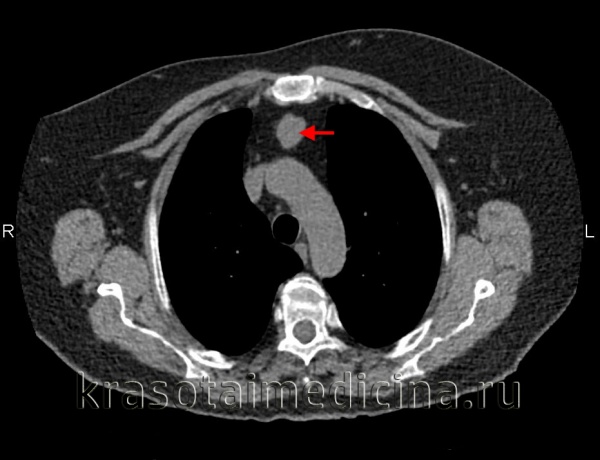

(а) Мужчина средних лет с жалобами на боли в груди. При рентгенографии органов грудной клетки в ПП проекции в левой половине переднего средостения определяется объемное образование с дольчатым контуром. На фоне образования визуализируется дуга аорты.

(б) У этого же пациента при КТ с контрастным усилением в преваскулярном отделе средостения выявляется объемное образование относительно гомогенной структуры с дольчатым контуром, локализующееся по обе стороны от срединной линии. Данное образование умеренно накапливает контрастное вещество. Медиастинальная семинома может имитировать конгломераты лимфатических узлов средостения при ходжкинской или неходжкинской лимфоме.